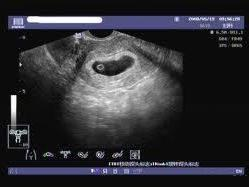

空孕囊是指孕婦在妊娠早期,胚胎發(fā)育異?;蛲V拱l(fā)育,導(dǎo)致孕囊內(nèi)沒有胚芽或胎心的情況,對于期待寶寶的家庭來說,空孕囊的出現(xiàn)無疑是一種打擊,了解空孕囊的征兆,早期識別并采取措施,對保障母嬰健康具有重要意義,本文將為您詳細解析空孕囊的十個征兆,以便您及時察覺并處理。

通過B超檢查發(fā)現(xiàn)胚胎未按照正常時間發(fā)育,如未按時出現(xiàn)胚芽、胎心等,可能是空孕囊的表現(xiàn)。

羊水是胎兒生長的重要環(huán)境,如B超檢查發(fā)現(xiàn)羊水過少或無羊水,可能是空孕囊的征兆。